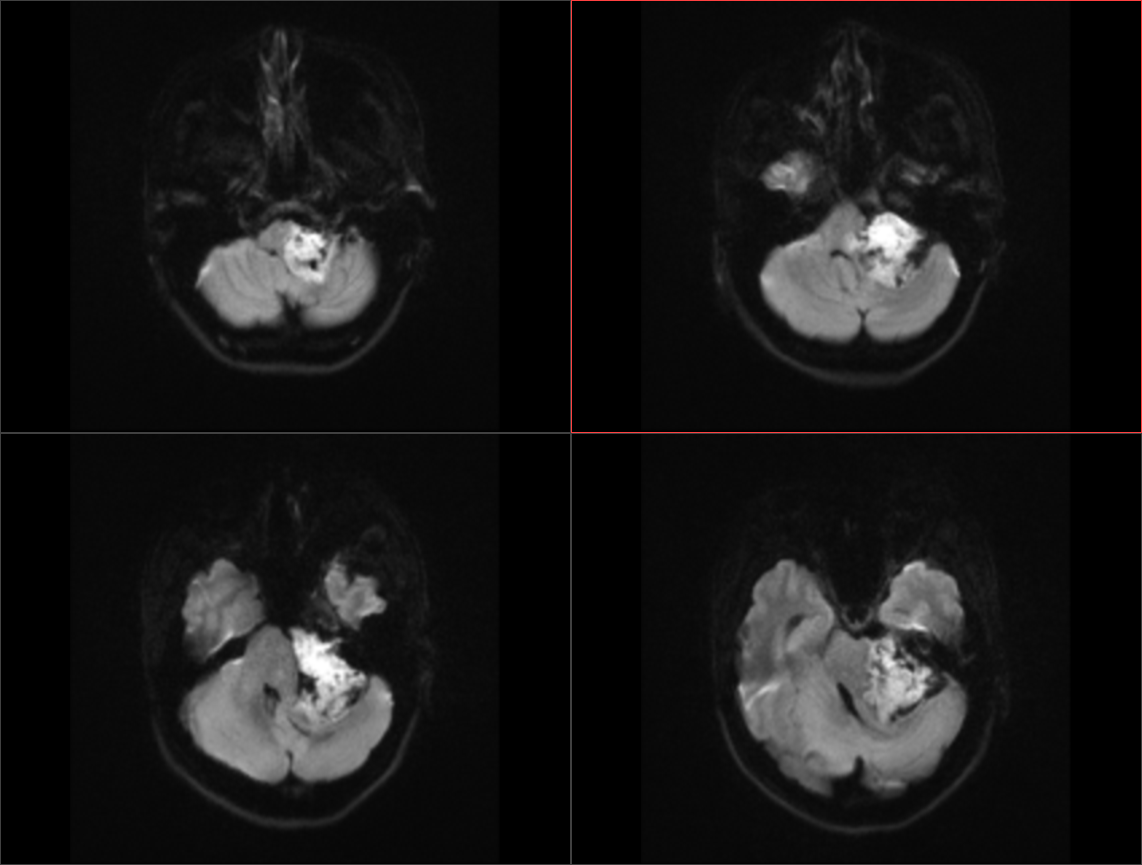

患者于入院前半年无明显诱因出现头痛、头晕,较剧烈,可耐受,无恶心、呕吐,无意识丧失,口服“止痛药(具体药名、剂量不详)”后症状稍缓解,入院前1周上述症状较前加重,患者前往当地医院就诊,行头颅MR示:1.左侧桥小脑角区占位,结合平扫及增强,现多考虑:皮样或表皮样囊肿。2。幕上梗阻性脑积水、脑室轻度积水。3.右侧上颌炎。现转至我院就诊。

术前影像: